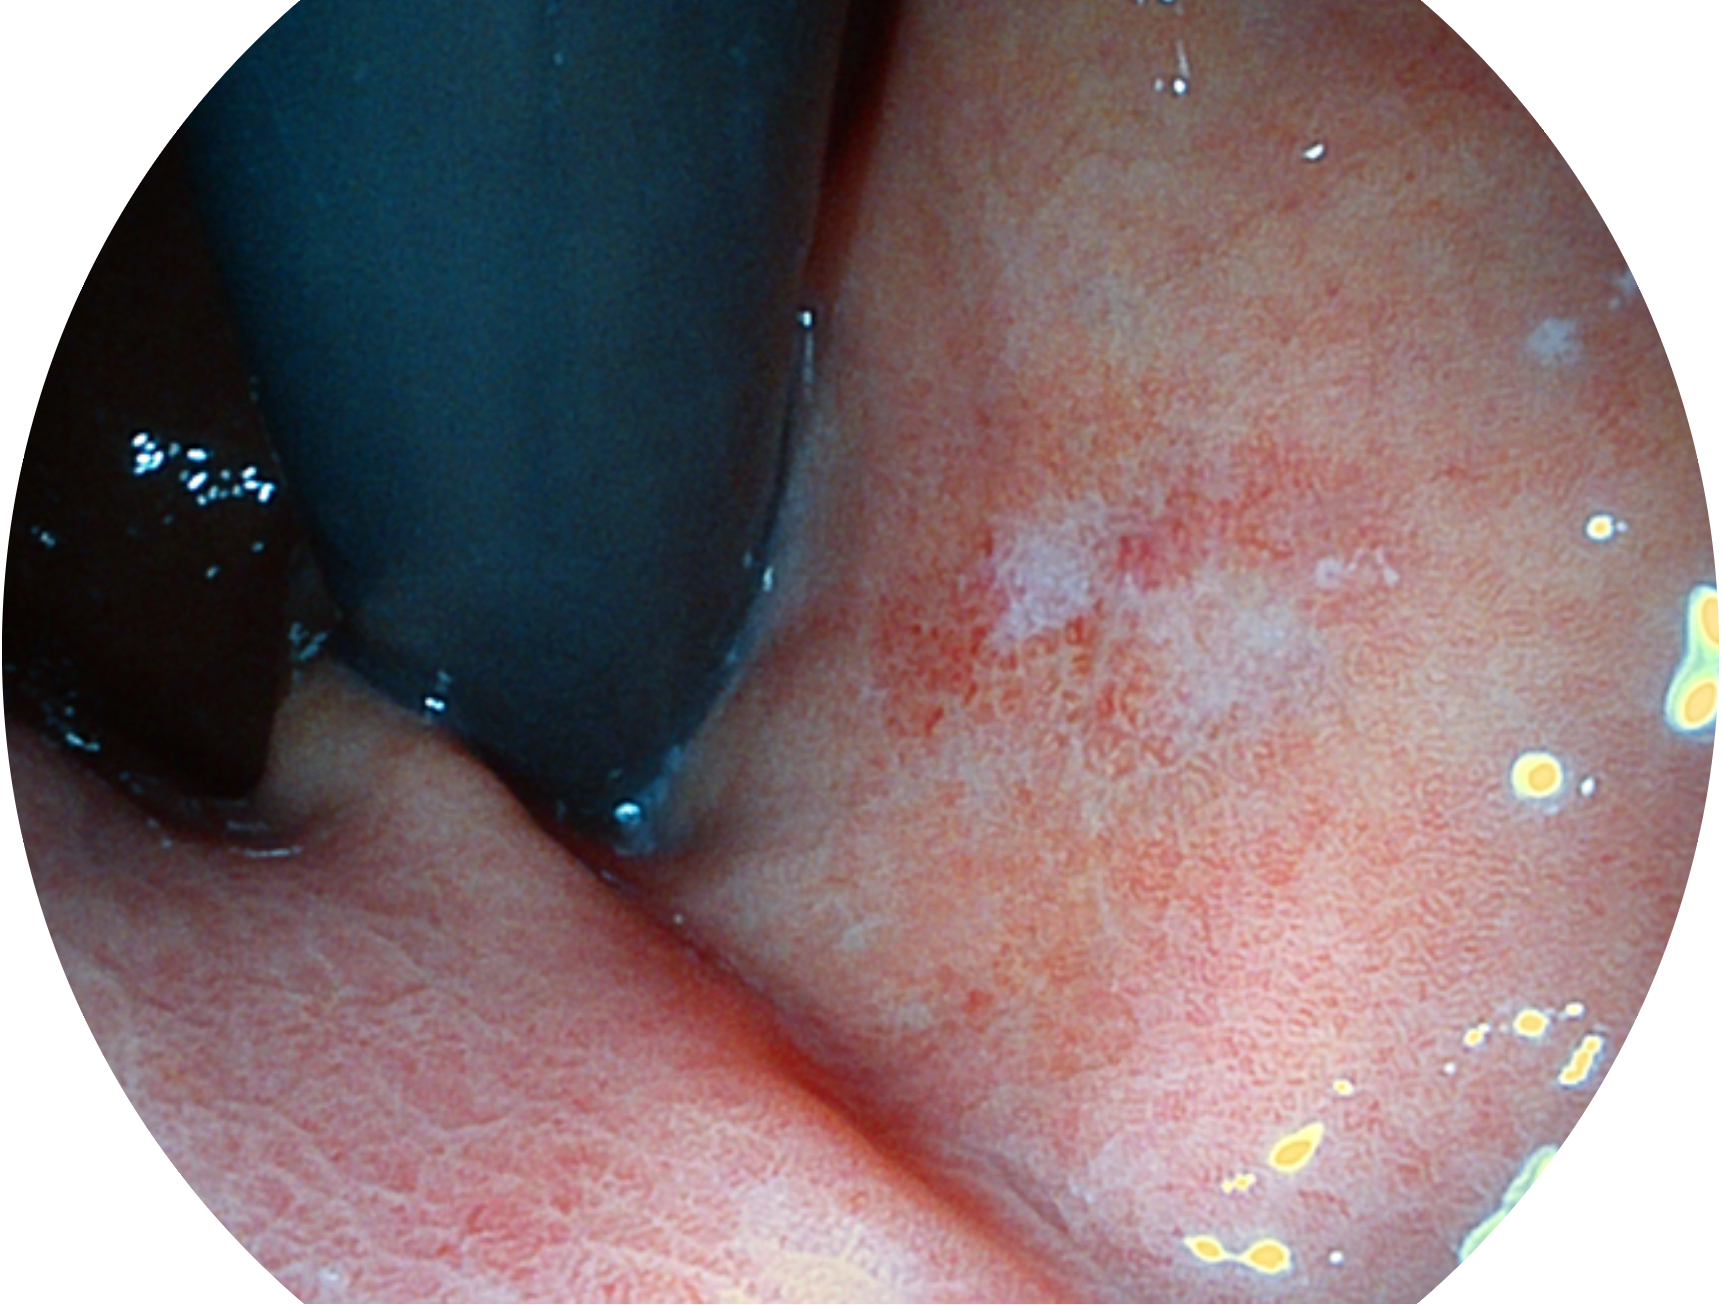

哈哈体育官网新开发的内镜染色技术,主要是基于多波长LED 光源的开发,VLS-55Q 四波长LED 光源是由四个不同颜色的LED光按照相应照明模式所规定的特定发光比例进行合束后形成,合束后形成的照明光的光谱由红光、绿光、蓝光及蓝紫光这四个不同的波段范围构成。具有更高光谱自由度,通过光谱比例的控制,实现了聚谱成像技术,英文全称为“Spectral Focused Imaging, SFI”,缩写为“SFI”和光电复合染色成像技术,英文全称为“Versatile Intelligent Staining Technology, VIST”,缩写为“VIST”。